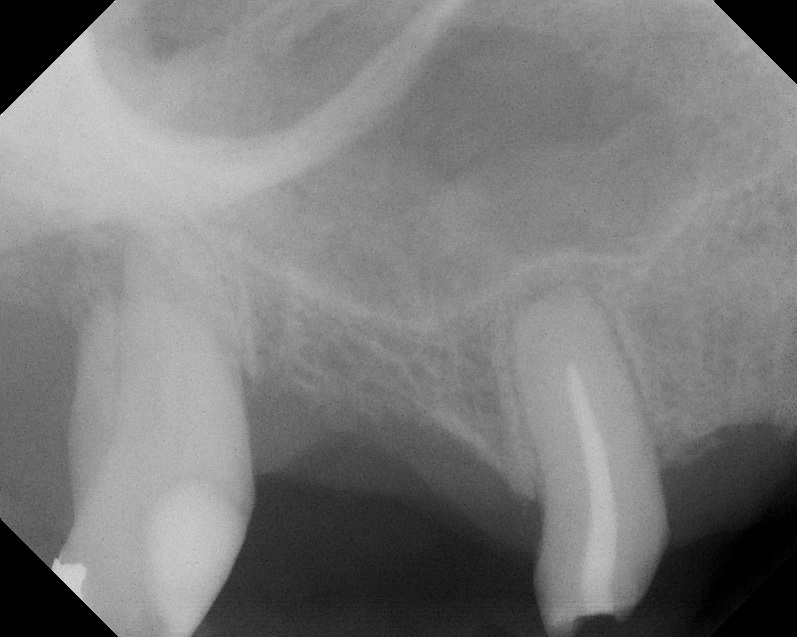

Case 3. Preoperative radiograph showing about 3.5 mm of ridge height.

Fig. 20

Day of sinus augmentation and implant placement in the No. 3 position. The sinus membrane has been raised about 7 mm to 8 mm.

Fig. 21

CBCT scan (Kodak 9000D) of No. 3 area, day of placement. Appearance of native bone and bone graft is clearly discernable.

Fig. 22

A 6.5-month postoperative radiograph. Teeth Nos. 2 and 4 have been extracted and an immediate implant had been placed in the No. 4 position.

Fig. 23

This patient was a 73-year-old man with only about 3.5 mm of native bone in the No. 3 site (Figure 20). The composite graft used here was a 50:50 mixture of DFDBA and deproteinized bovine bone mineral (Osteohealth, www.osteohealth.com) with approximately 40% calcium sulfate added. The implant was the same type and length as in Case 1 above. Figure 21 shows the area on the day of placement. In the CBCT scan on the day of placement (Figure 22), the native bone and bone graft were clearly discernable. However, the postoperative radiograph taken at 6.5 months (Figure 23) showed no marginal bone loss and a significantly denser appearance than when the graft was place. The membrane was raised about 7 mm to 8 mm. The final radiograph was taken after extraction of tooth No. 2 and after extraction of tooth No. 4 and immediate implant placement.